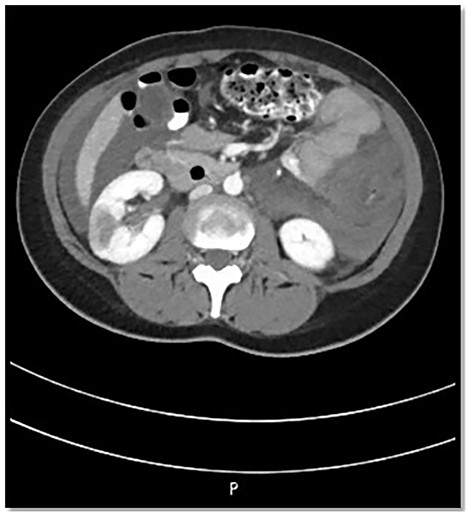

The patient was admitted to Surgical Intensive Care Unit (SICU) for hemodynamic monitoring and after a few hours of monitoring, she developed tachycardia, drop in hemoglobin and platelet count. Computed tomography (CT) angiogram abdomen was done that revealed hyperdense ascites, likely hemoperitoneum, nonenhancement of the sigmoid, descending, transverse and ascending colon along with the terminal ileum along with fat stranding suggestive of ischemia; however, there was no air in the mucosal wall or within the portal venous system. Also, Portal Vein (PV) and Superior Mesenteric Vein (SMV) thrombosis and bilateral kidneys wedge-shaped cortical hypodensities (mainly suggest ischemic insult) (Fig. 1).

CT abdomen findings show significant thickening of the transverse colon with significant pericolic fat stranding; the right kidney shows wedge-shaped cortical hypodensities (could represent ischemic insult).